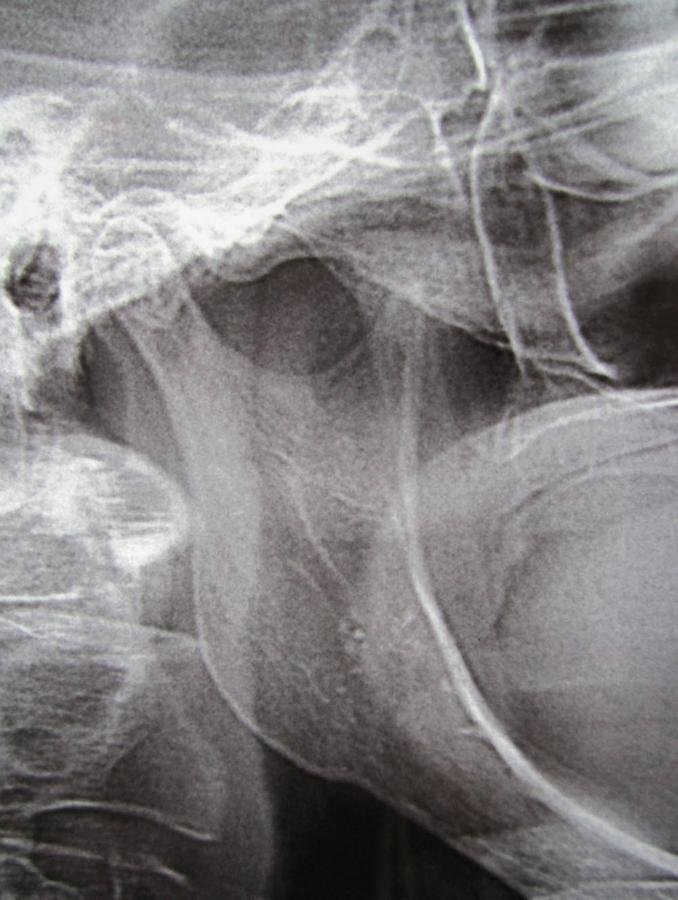

Radiografía panorámica

Julio 5 de 2014

DIAGNÓSTICO ATM

Desplazamiento anterior del disco

con reducción